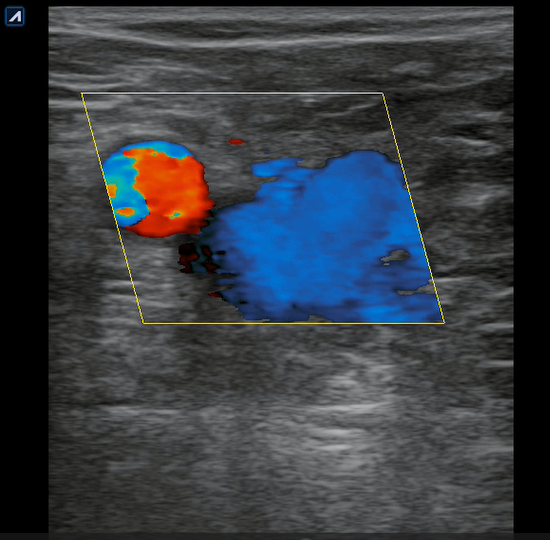

Se realiza ecografía clínica en consulta donde observamos a nivel inguinal adecuada compresibilidad de vena femoral y relleno con Doppler color. Cayado de safena libre y compresible. A 7 cm de distancia del cayado se aprecia, en territorio de safena, dilatación no compresible de la misma, contenido intraluminal ligeramente ecogénico y ausencia de Doppler color compatible con trombosis venosa superficial de 19 cm de distancia. Se estudia recorrido donde se observa en zona de dilataciones varicosas material ecogénico con ausencia de paso de Doppler alternando con zonas de paso parcial. En tercio distal de muslo comienza a desaparecer. Vena femoral profunda, poplítea y perforantes sin datos de trombosis.